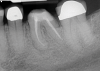

(8.) An original finding of a small lesion on the mesial root of tooth No. 30 was not accompanied by any outward symptoms; therefore, the patient delayed pursuing treatment. When a follow-up CBCT scan was acquired 6 years later, the easy-to-visualize increase in the dimensions of the lesion motivated the patient to elect a treatment plan.

Figure 8

(9.) An original finding of a small lesion on the mesial root of tooth No. 30 was not accompanied by any outward symptoms; therefore, the patient delayed pursuing treatment. When a follow-up CBCT scan was acquired 6 years later, the easy-to-visualize increase in the dimensions of the lesion motivated the patient to elect a treatment plan.

Figure 9

Identifying the shape and location of the roots of teeth to be removed is critical to performing safe exodontia. Some clinicians virtually deconstruct teeth using CBCT images prior to actually sectioning and removing them. Being able to recognize pathoses and differentiate affected structures from normal structures is key in deciding what the treatment should be and when that treatment should be initiated (Figure 8 through Figure 10). The arena of the oral surgeon is larger than that of many general practitioners, involving the sinuses and condyles and other considerations in and around the entire mandible and maxilla. Certain fractures and other conditions that some general practitioners feel uncomfortable treating are often referred for evaluation and treatment by an oral surgeon. Because of this, oral surgeons require the most accurate and complete diagnostic information available. The American Academy of Oral and Maxillofacial Radiology recommends that "cross-sectional imaging be used for the assessment of all dental implant sites" and has stated that "CBCT is the imaging method of choice for gaining this information."18